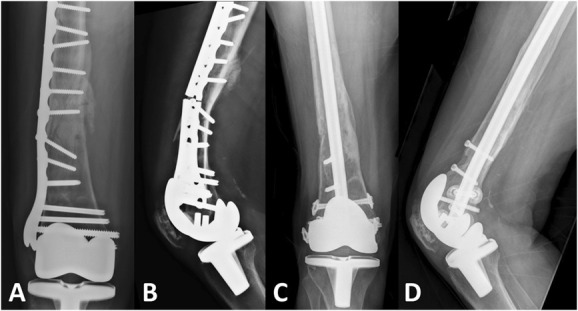

Distal femur fractures are challenging injuries to manage, and complication rates remain high. This article summarizes the international and basic science perspectives regarding distal femoral fractures that were presented at the 2022 Orthopaedic Trauma Association Annual Meeting. We review a number of critical concepts that can be considered to optimize the treatment of these difficult fractures. These include biomechanical considerations for distal femur fixation constructs, emerging treatments to prevent post-traumatic arthritis, both systemic and local biologic treatments to optimize nonunion management, the relative advantages and disadvantages of plate versus nail versus dual-implant constructs, and finally important factors which determine outcomes. A robust understanding of these principles can significantly improve success rates and minimize complications in the treatment of these challenging injuries.